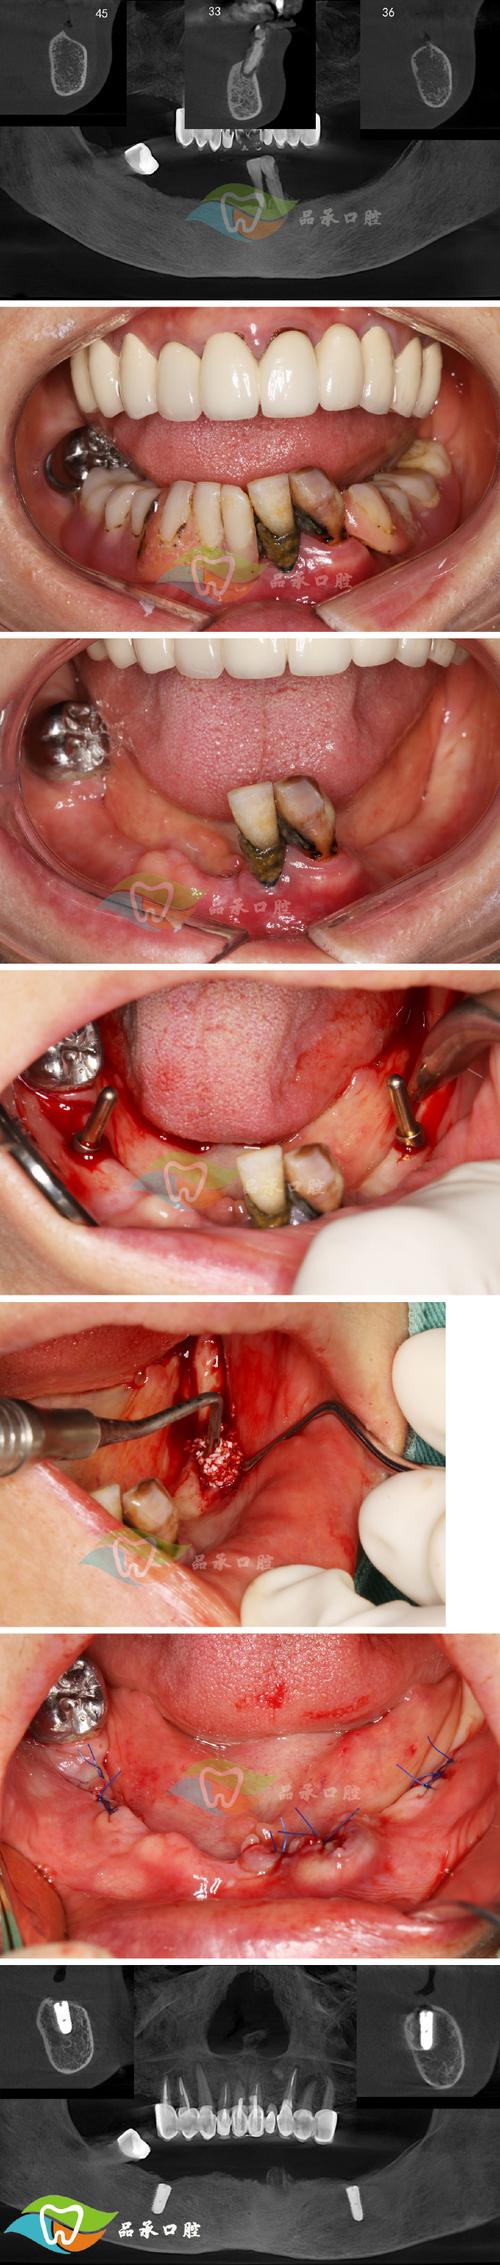

种植体周围炎:

- 原因: 这是种植体周围软硬组织的慢性炎症,类似于天然牙的牙周炎,主要原因是口腔卫生维护不当导致菌斑堆积,刺激炎症反应,进而破坏支撑种植体的牙槽骨。

- 症状: 种植体周围牙龈红肿、出血、溢脓、牙周袋形成、种植体周围骨吸收、种植体松动。

- 处理: 强调预防为主!一旦发生,治疗难度大,包括专业的机械清创(刮治)、激光治疗、必要时手术翻瓣清创、骨增量等,严重时可能需要取出种植体。

- 预防: 患者终身良好的口腔卫生习惯是关键! 正确使用牙线、牙缝刷、冲牙器等,并定期(至少每年1-2次)进行专业的种植体维护(洁治和刮治)。